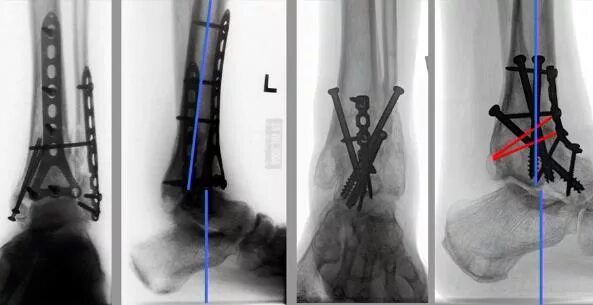

Артродез форум